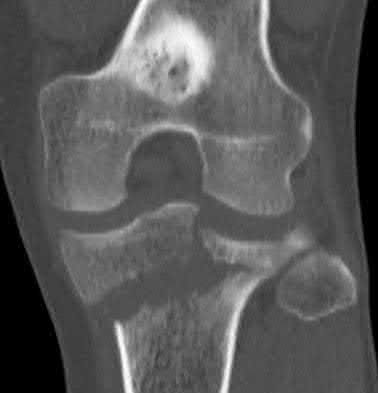

2. # A 35-year-old woman is involved in a head-on collision while driving. Initial radiographs are shown in Figures 8a and 8b. Injury to what vessel increases the risk for osteonecrosis of the injured bone?

1. Dorsalis pedis artery

2. Perforating peroneal artery

3. Lateral tarsal artery

4. Artery of the tarsal canal

5. Artery of the tarsal sinus Corrent answer: 4

The patient has a Hawkins type III talar neck fracture-dislocation with a risk of osteonecrosis ranging from 69% to 100%. Anatomic studies have shown that the artery of the tarsal canal supplies the lateral two thirds of the talar body.

The other vessels listed provide no significant contribution to the talus.